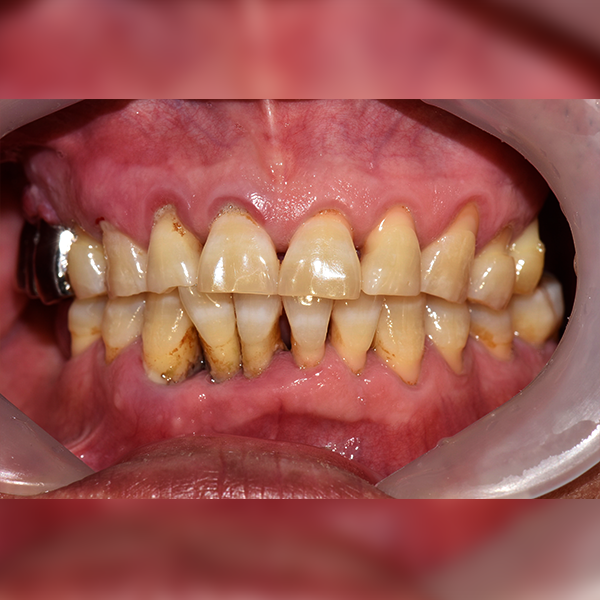

3. Trường hợp 239 Ông/Bà Lee*gan, 50 tuổi 2019-01-11 / 2019-07-24

Trường hợp 239 Ông/Bà Lee*gan, 50 tuổi 2019-01-11 / 2019-07-24

Before Before

After After